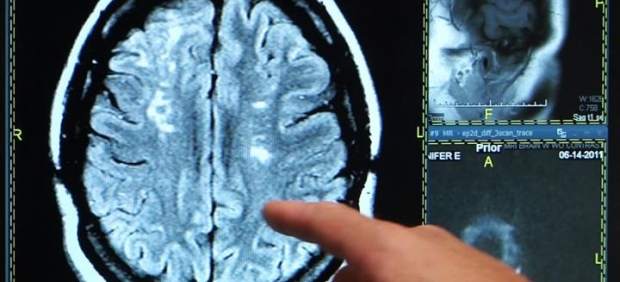

En el hospital, a través de un escáner, se determinará si se trata de un infarto cerebral o ictus esquémico (producido por el taponamiento o la oclusión de una arteria debido a un coágulo y suponen alrededor del 80 % de los ictus) o de una hemorragia cerebral, causada por la ruptura de un vaso.